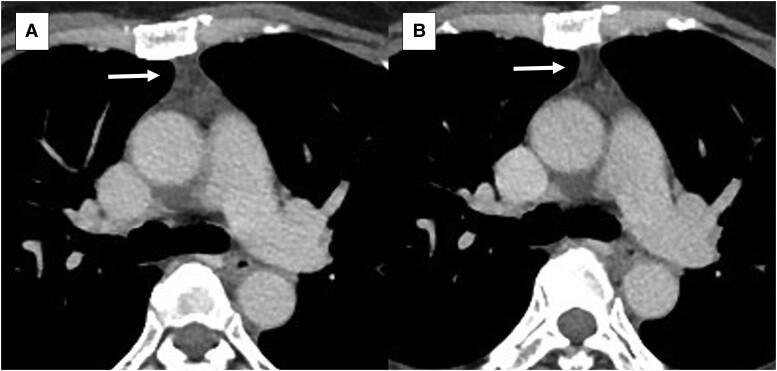

Thymic hyperplasia has occasionally been reported in patients with Graves disease (GD). However, ectopic cervical thymic hyperplasia in the setting of hyperthyroid GD is exceptionally rare. We describe a case of a 54-year-old Thai woman who presented with hyperthyroidism, diplopia, and pretibial myxedema. She underwent a total thyroidectomy because of diplopia caused by Graves ophthalmopathy. During the surgery, 3 macroscopically abnormal enlargements of parathyroid gland-like tissue were identified and removed. Histopathology revealed hyperplastic thymic tissue mixed with 1 normal-sized parathyroid gland at the location of the left upper parathyroid gland, and thymic tissue was found in the sample labeled as the right upper parathyroid gland. Notably, the sample labeled as the right lower parathyroid gland was actually determined to be a lymph node. Preoperative blood samples showed normal serum calcium and parathyroid hormone levels. Postoperatively, computed tomography of the chest showed thymic hyperplasia in the anterior mediastinum, which slightly regressed at the 9-month follow-up. The patient had transient hypoparathyroidism requiring oral calcium and active vitamin D supplements for 6 months postoperatively. Ectopic cervical thymic hyperplasia can be found in GD and might be indistinguishable from parathyroid hyperplasia. Biochemical evaluations are required to exclude concomitant hyperparathyroidism, and a conservative approach should be considered.